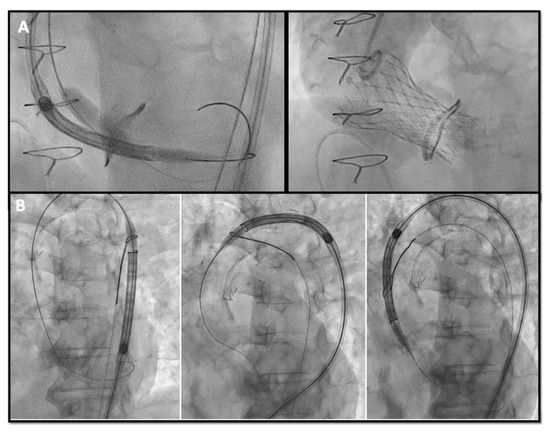

- The timing of BVF, either before or after TAVR, remains controversial. BVF after THV implantation leads to better hemodynamics but carries a risk of damaging new prosthesis; BVF before THV implantation ensures better sealing, but may cause embolization of SHV, acute valvular regurgitation and hemodynamic instability [40,41]. The general practice is to do BVF after THV if using BEV so the NC balloon simultaneously fully expand the THV and fracture the surgical prosthesis while SEVs may not have enough force to fully expand a degenerated SHV and will benefit from balloon fracture before and if needed, even after implantation (Figure 6).

Figure 6. (A) Bioprosthetic valve fracture with a True Balloon 20 balloon after valve-in-valve with Corevalve Evolut Pro + n.23 implantation in a Mitroflow 19 (LCA protection without final stent implantation) (B) IVUS shows patency of the VS with a minimum distance between aortic wall and prosthetic leaflet of 2.2 mm at STJ. LCA: left coronary artery; IVUS: intra-vascular ultrasound; STJ: sino-tubular junction distance.